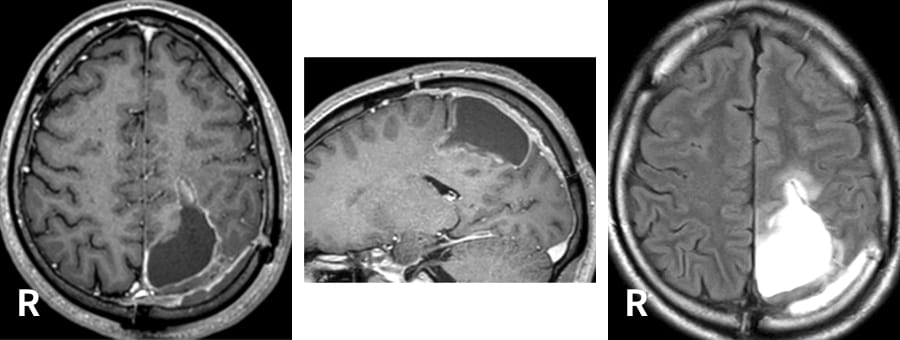

元々は中脳の右腹側(前側)の血管腫で、出血を繰り返した例。

水頭症を伴い、意識障害、眼球運動障害、左麻痺を生じた。手術前に入念にシミュレーションを行い、右側の頬骨と眼窩縁を外してのアプローチにより、大部分の摘出がなされた。

手術後、水頭症は消失し、現在までのところは再出血はなく、ADL(日常生活動作)自立となった。

術前

術後